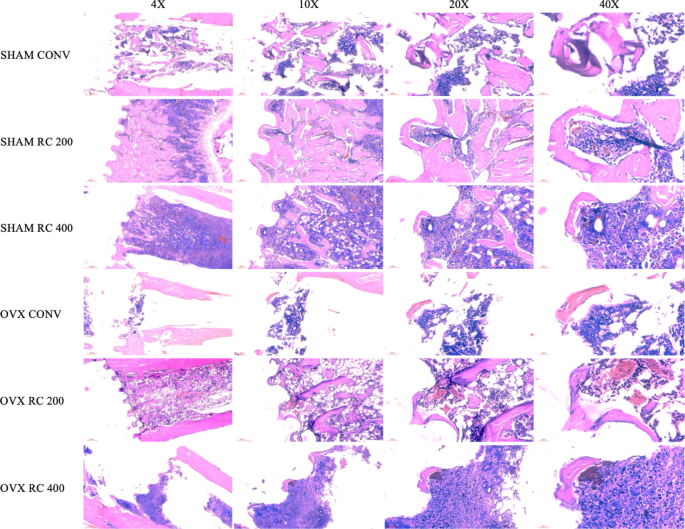

Histological analysis was conducted at 28 days post-implantation. In SHAM rats, the RC 200 surface promoted greater corticalization of the bone in contact with the implant, compared to the other groups, including the CONV implant. In contrast, the RC 400 surface exhibited a significant amount of adipose tissue (Fig. 3). In OVX rats, a similar pattern was observed. The RC 200 surface demonstrated enhanced bone corticalization and maturation of the peri-implant bone, while the other surfaces exhibited less newly formed bone (Fig. 3).

Histological images of experimental groups. SHAM CONV, SHAM RC 200, SHAM RC 400, OVX CONV, OVX RC 200, and OVX RC 400 groups are shown at magnifications of 4X, 10X, 20X, and 40X. Note that the groups treated with RC 200 exhibited a greater amount of mineralized bone surrounding the implant threads compared to the other groups.